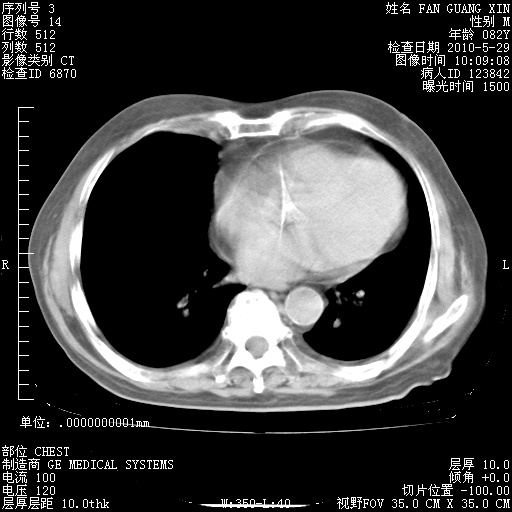

再治疗10天后的肺部CT 纵膈窗

阅读此次胸部CT,肺间质渗出性改变较入院时有吸收。目前从体温、白细胞、中性分叶明显增高,肯定存在细菌感染(发生医院感染哦,若无消化道及泌尿系统等感染的依据,肺部感染可能大)。若你院头孢哌酮舒巴坦钠耐药率较高,同意你的方案,若48小时体温仍高,可考虑使用碳青霉稀类抗菌药物,同时可予超声雾化、注意滴数时加大液体量。白蛋白33.30g/L较低哦,需加强营养等支持治疗。